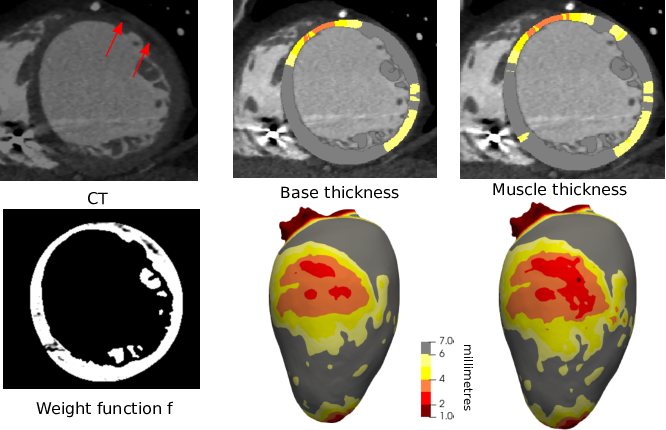

Figure 4: Myocardium-only thickness. From left to right: (top) CT image showing fat inclusions in the left myocardium (red arrows); (bottom) result of f(x); non-weighted thickness; weighted thickness showing more severe thinning. The thicknesses are shown both on a 2D slice (top) and projected on a surfacic mesh of the ventricular wall.

Fat and calcification inclusions in the myocardium are common. Evaluating the thickness of the muscle fibers excluding these inclusions is the most straightforward application of our method.

The Houndsfield units (HU) of muscle and fat are close, especially in the context of iodine-injected CT. After segmentation, we performed a histogram analysis of HU values within the myocardium to determine the peak value \(P\), and standard deviation \(\delta\). We define a transfer function to set \(f(x)\) depending on the HU such that:

An example result is shown on fig. 4.